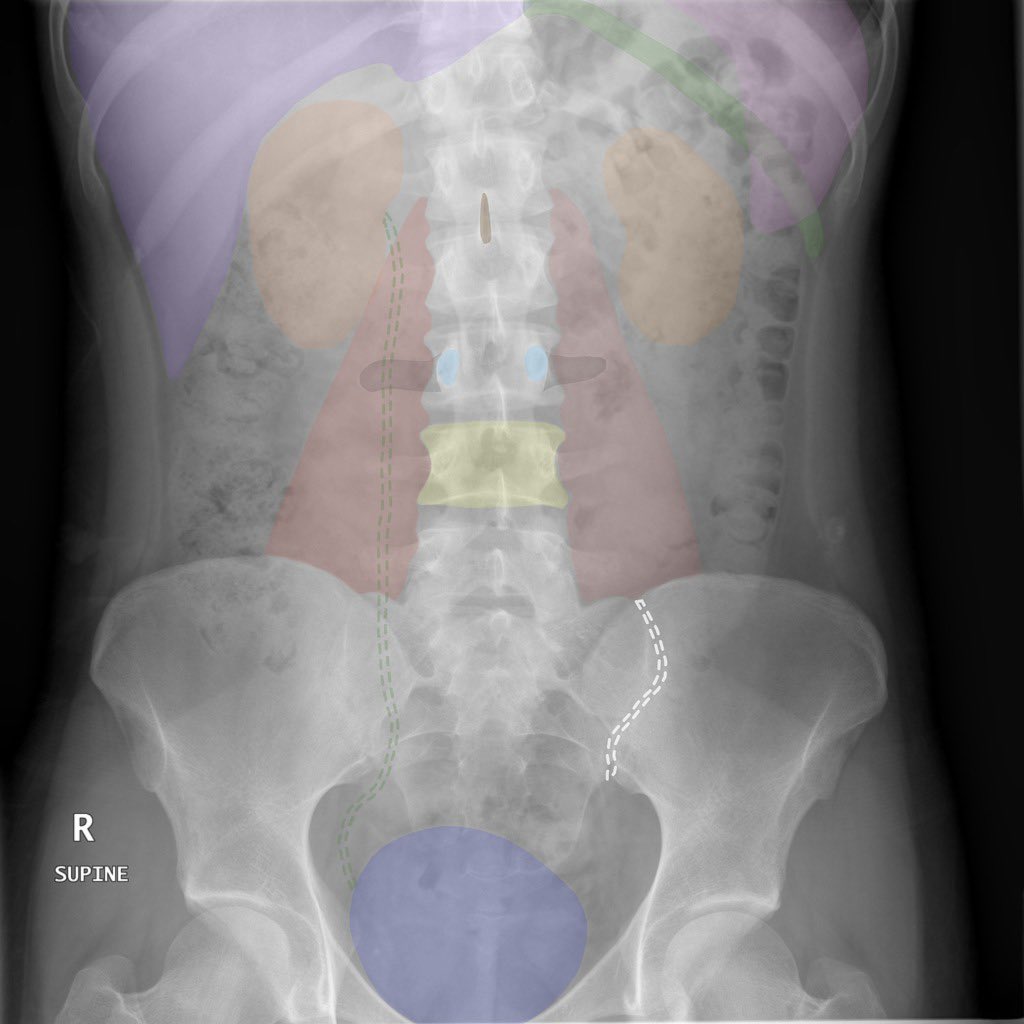

الأشعة المقطعية للبطن 🌟👇🏻

Abdominal CT